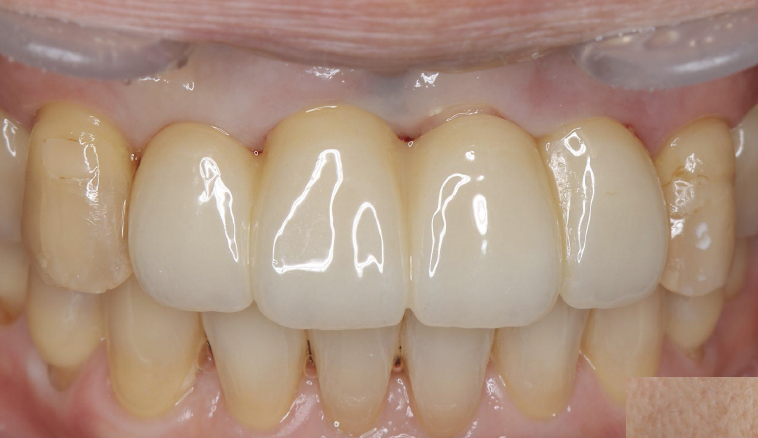

抜歯、インプラント埋入から6か月後に完成しました。

歯周病には気をつけてたつもりでしたけど、気づいたら前歯4本を抜くことに…。正直どうなるか分からなくて不安でした。見た目も心配でしたが、抜歯と同時に治療してもらえて、思ったより落ち着いて過ごせました。無事に治療が終わって、今はほっとしています。